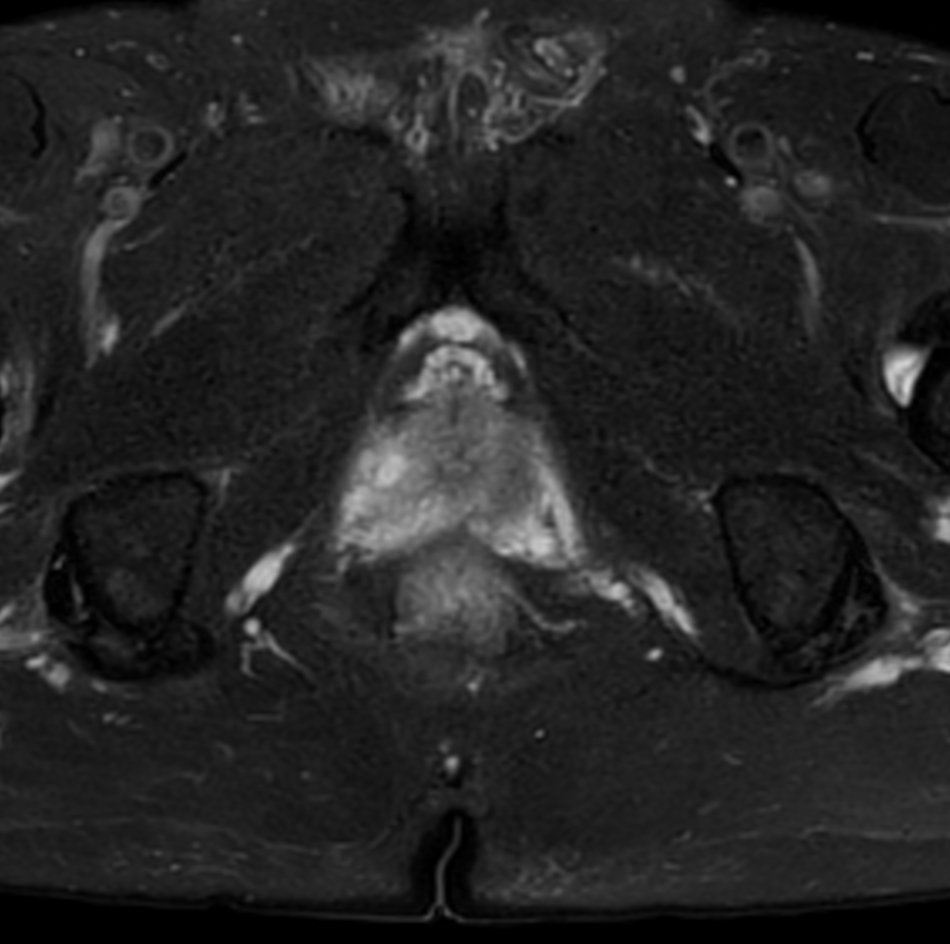

Prostate lesion with fat-free mDIXON XD imaging